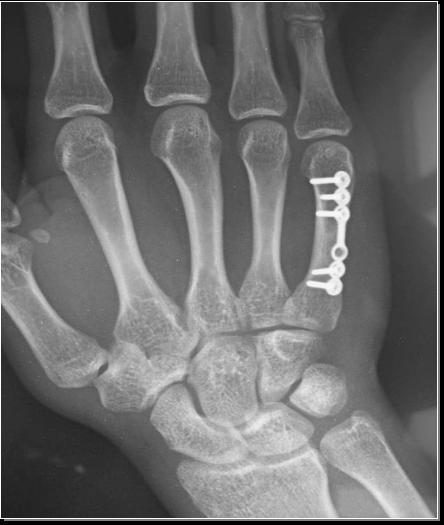

掌骨骨折十级伤残图片

掌骨骨折十级伤残图片,十级伤残图片

掌骨骨折的治疗

掌骨骨折

掌骨骨折图片

第一掌骨基底部骨折

第一掌骨骨折

掌骨骨折九级伤残图片

第四掌骨骨折

掌骨骨折手术

掌骨骨折长骨痂图片